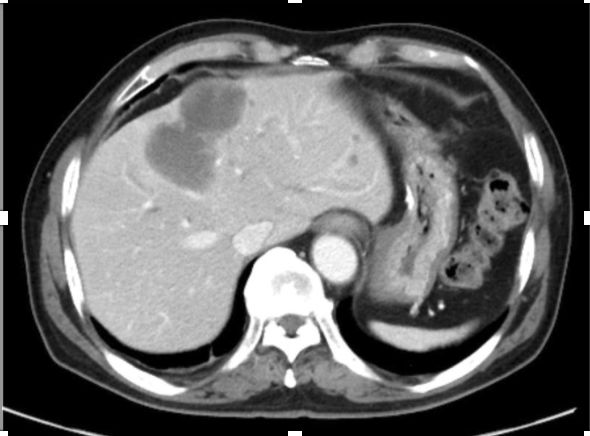

经典个案

1. 胃肠道间质瘤术后肝多形性平滑肌肉瘤一例报告

Hepatic pleomorphic leiomyosarcoma after surgery for gastric gastrointestinal stromal tumor: a case report

Ryo Muranushi, Kouki Hoshino, Kei Hagiwara, et al.

Department of General Surgical Science, Division of Hepatobiliary and Pancreatic Surgery, Graduate School of Medicine, Gunma University

Surg Case Rep. 2019 Apr 16;5(1):62. doi: 10.1186/s40792-019-0622-9.

摘要:

背景:多形性平滑肌肉瘤(PLMS)是极为罕见的肿瘤。我们报告了第一例胃肠道间质瘤(GIST)术后肝原发性PLMS。病例:病人是一名62岁的男性,切除了胃GIST手术后产生的肝肿瘤,该肿瘤对伊马替尼和舒尼替尼耐药,肝左叶有一个40毫米的肿瘤,右叶有三个小结节,进行了肝左叶和其余三个病变切除,根据组织病理学和免疫组化结果及c-kit基因突变分析,主要肿瘤诊断为PLMS。结论:有必要考虑伊马替尼耐药的GIST复发性病变是一种不同类型的软组织肉瘤的可能。准确的诊断是必需的,不要错过机会根治性切除PLMS。

浙江省肿瘤医院

结直肠外科 朱玉萍教授

多形性平滑肌肉瘤占平滑肌肉瘤的10%, PLMS通常由老年人的骨骼肌或腹膜后组织起源,预后非常差,具有高度侵袭性。原发性肝PLMS非常罕见,占肝脏所有恶性肿瘤的0.5-2%。这例case报道的是既往诊断GIST,术后2年出现肝脏出现病灶,且在影像学考虑转移,形态非常符合GIST术后肝转移(如下图),而后并未对肝转移灶进行穿刺诊断,进行伊马替尼的治疗,在治疗无效后考虑是否存在原发耐药及其他肉瘤可能,进而进行手术治疗,术后病理组织学诊断PLMS明确。从这个病例汇报,我们可以看到,很多的肝脏的肉瘤在影像学表现相似,在治疗前,需要考虑既往病史的情况下,有必要进行穿刺再次明确病理,以区别一些相混淆的情况,另外对于耐药的转移性GIST患者而言,更要把握手术根治性切除的机会。